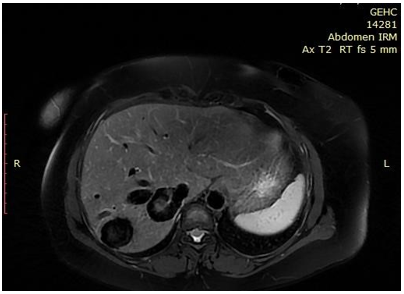

Intrahepatic Portosystemic Venous Shunt: A Case Report

M Jaddour, K Imrani, N Moatassimbillah and I Nasser. 7(3): 01-04.